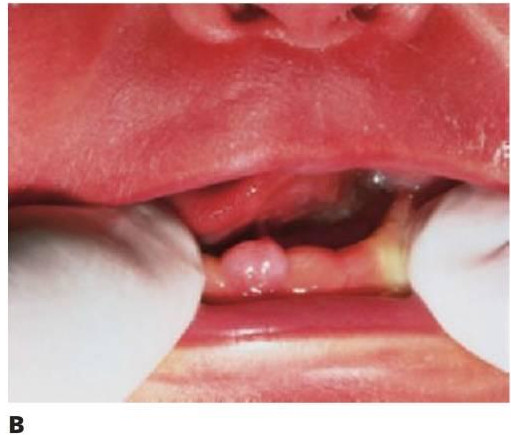

Dientes supernumerarios

Los dientes supernumerarios surgen como resultado de una geminación de la lámina dental que se produce de forma esporádica o se heredan, como sucede con la displasia cleidocraneal (fig. 9.8).

La forma de los dientes puede recordar a la forma de las piezas normales (diente suplementario), es decir, incisiforme, caniniforme o molariforme; de no ser así, sería cónico o tuberculado.

Habitualmente se presenta como consecuencia del fallo en la erupción de uno o más dientes permanentes y en general presenta formas cónicas o tuberculadas.

Diagnóstico

- Erupción fallida o ectópica de un diente permanente (fig. 9.8B).

Tratamiento

- A menudo erupcionan dientes cónicos que se pueden extraer con mucha facilidad (fig. 9.8A).

- Los dientes tuberculados o cónicos invertidos requieren extracción quirúrgica (fig. 9.8D) tan pronto como sea posible para permitir la erupción sin obstáculos del diente permanente.